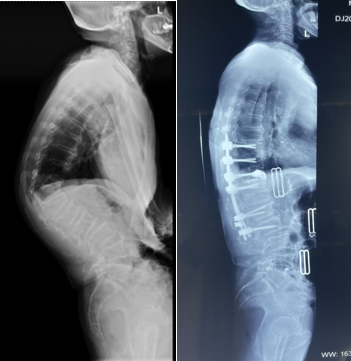

经过周密的术前准备工作,2022年9月27日,孙海燕主任带领团队人员在麻醉手术室、输血科等科室的通力配合下为患者实施手术。术中,行多节段Ponte截骨和T12椎体SPO截骨,椎板切除,椎管扩大减压、内固定植骨融合等,经过4个小时的努力,手术顺利完成,术中出血约400ml,神经电生理监测无神经并发症,取得非常好的矫形和减压效果。

(术前术后对比图)

患者术后第5天可自行站立,外形纠正良好,胸腹部受压解除,在脊柱二科医护人员的精心照护下,患者伤口愈合良好,家人们都激动不已,多次对孙主任团队表示感激之情。